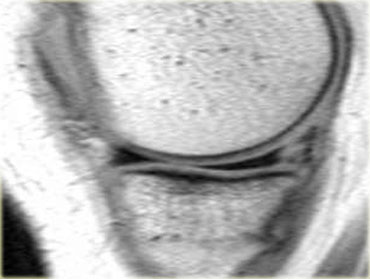

Đây là một trường hợp rách chân sụn chêm trong khác.

Lưu ý rằng sừng sau không còn bám vào xương chày.

Thay vào đó, có thể thấy một khoảng hở (mũi tên cong).

Những tổn thương rách này rất dễ bị bỏ sót khi người đọc nhầm tưởng sừng sau vẫn bình thường.

Đây là một trường hợp điển hình khác của rách chân sụn chêm trong.

Lưu ý rằng trường hợp này còn kèm theo hình ảnh sụn chêm ngoài dạng đĩa.